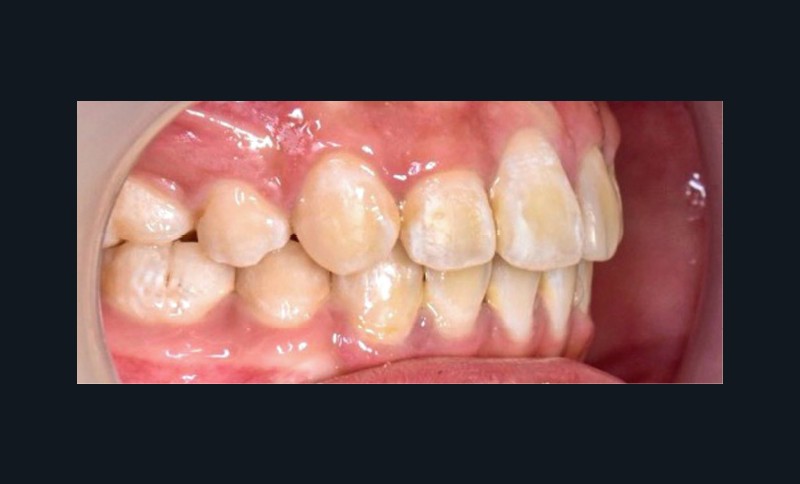

Une patiente âgée de 12 ans se présente en consultation, motivée par la position de son incisive centrale maxillaire, décrite comme « en avant », marquée par une dyschromie et une mobilité de grade 2 selon Muhlemann. L’examen clinique montre l’absence de 23 sur l’arcade, une dysharmonie dents-arcade marquée, un surplomb accentué, et une déviation des milieux inter-incisifs, conséquence du comblement spontané de l’espace de 23. L’ensemble s’inscrit dans un contexte de Classe I d’Angle molaire. L’orthopantomogramme révèle l’inclusion de 23, associée à une résorption radiculaire étendue aux deux tiers de 21. La 22 ne présente aucune altération visible.

La patiente, de profil normodivergent, présente une Classe I squelettique sans troubles fonctionnels (fig. 1-8).